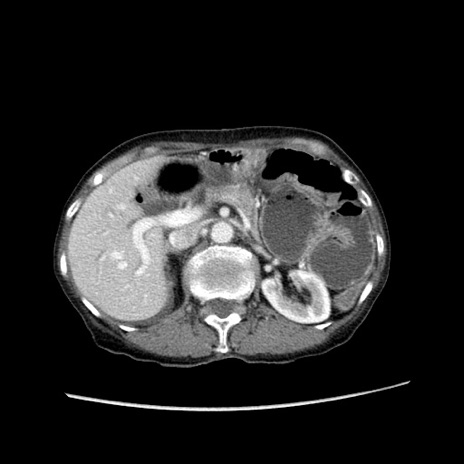

症例25(横断像)

【症例】80歳代女性

【主訴】胸のつかえ感

【現病歴】約9時間前に食後から胸のつかえた感じあり、嘔吐あり、来院。

【既往歴】胃癌(全摘)、胆摘、虫垂炎

【身体所見】心窩部に圧痛あり、反跳痛なし。

【データ】WBC 5700、CRP 0.05